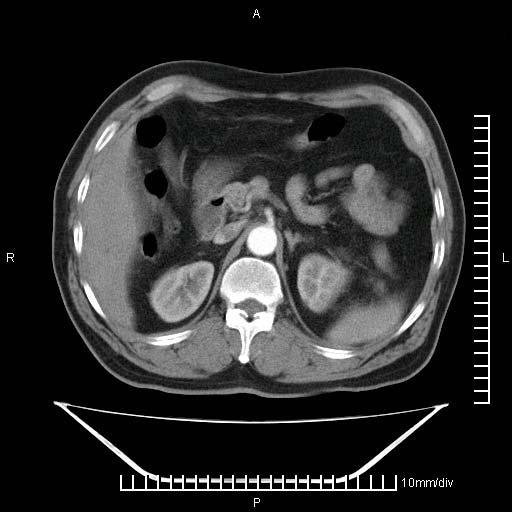

标题: CT25082:肝脏增强:男性,70岁 [打印本页]

标题: CT25082:肝脏增强:男性,70岁

患者以心脏疾病收住院,腹部无明显症状,b超查肝脏有占位。

肝内多发转移瘤,右下肺炎症并少量胸水。胃壁增厚建议胃镜,胰尾部“病变”为肠管。

1)肝脏多发性转移瘤(不排除胰尾癌转移所致可能)。2)腹水。3)右侧少量胸腔积液。

胰尾占位?结肠脾曲?

ct25082 结果:转移瘤

外院mr结果:胰尾恶性占位。

肝多发低密度灶;轻度强化,较水密度高,考虑转移,不排除肝脓肿